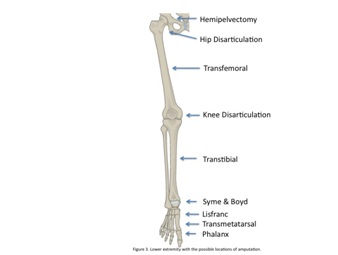

The lower extremity has a myriad of locations where amputation is an option (Table 1); the most common lower extremity amputation is the transtibial while the least is the transpelvic amputation [6]. Proximal lower extremity amputations, the hemipelvectomy and hip disarticulation, have an extremely high mortality rate, reported as high as 50% [7]. Advances in anesthesia and surgical technique have drastically decreased these numbers to 0-10% [8].

Amputation of the lower extremity is a common procedure performed by orthopedic surgeons at various levels for pathology ranging from tumor to sepsis to trauma. Treating patients with amputation requires not only ample knowledge of anatomy, but also a thorough understanding of gait biomechanics along with the current state of prosthetics and orthotics. Understanding the options for lower extremity amputation is an important part of an orthopedic surgeon’s armamentarium as it allows for the ideal surgical procedure to be performed that maximizes optimal post-operative function and rehabilitation (Figure 3). Treating the whole patient by assessing pre-operative functional status, evaluating medical co-morbidities, and reviewing the surgical pathology requiring amputation will help the surgeon and patient come to a consensus decision on the operation to be performed and rational functional goals post-operatively. Teamwork when treating amputees remains paramount for a successful return to function.

Figure 3: Lower extremity with the possible locations of amputation.